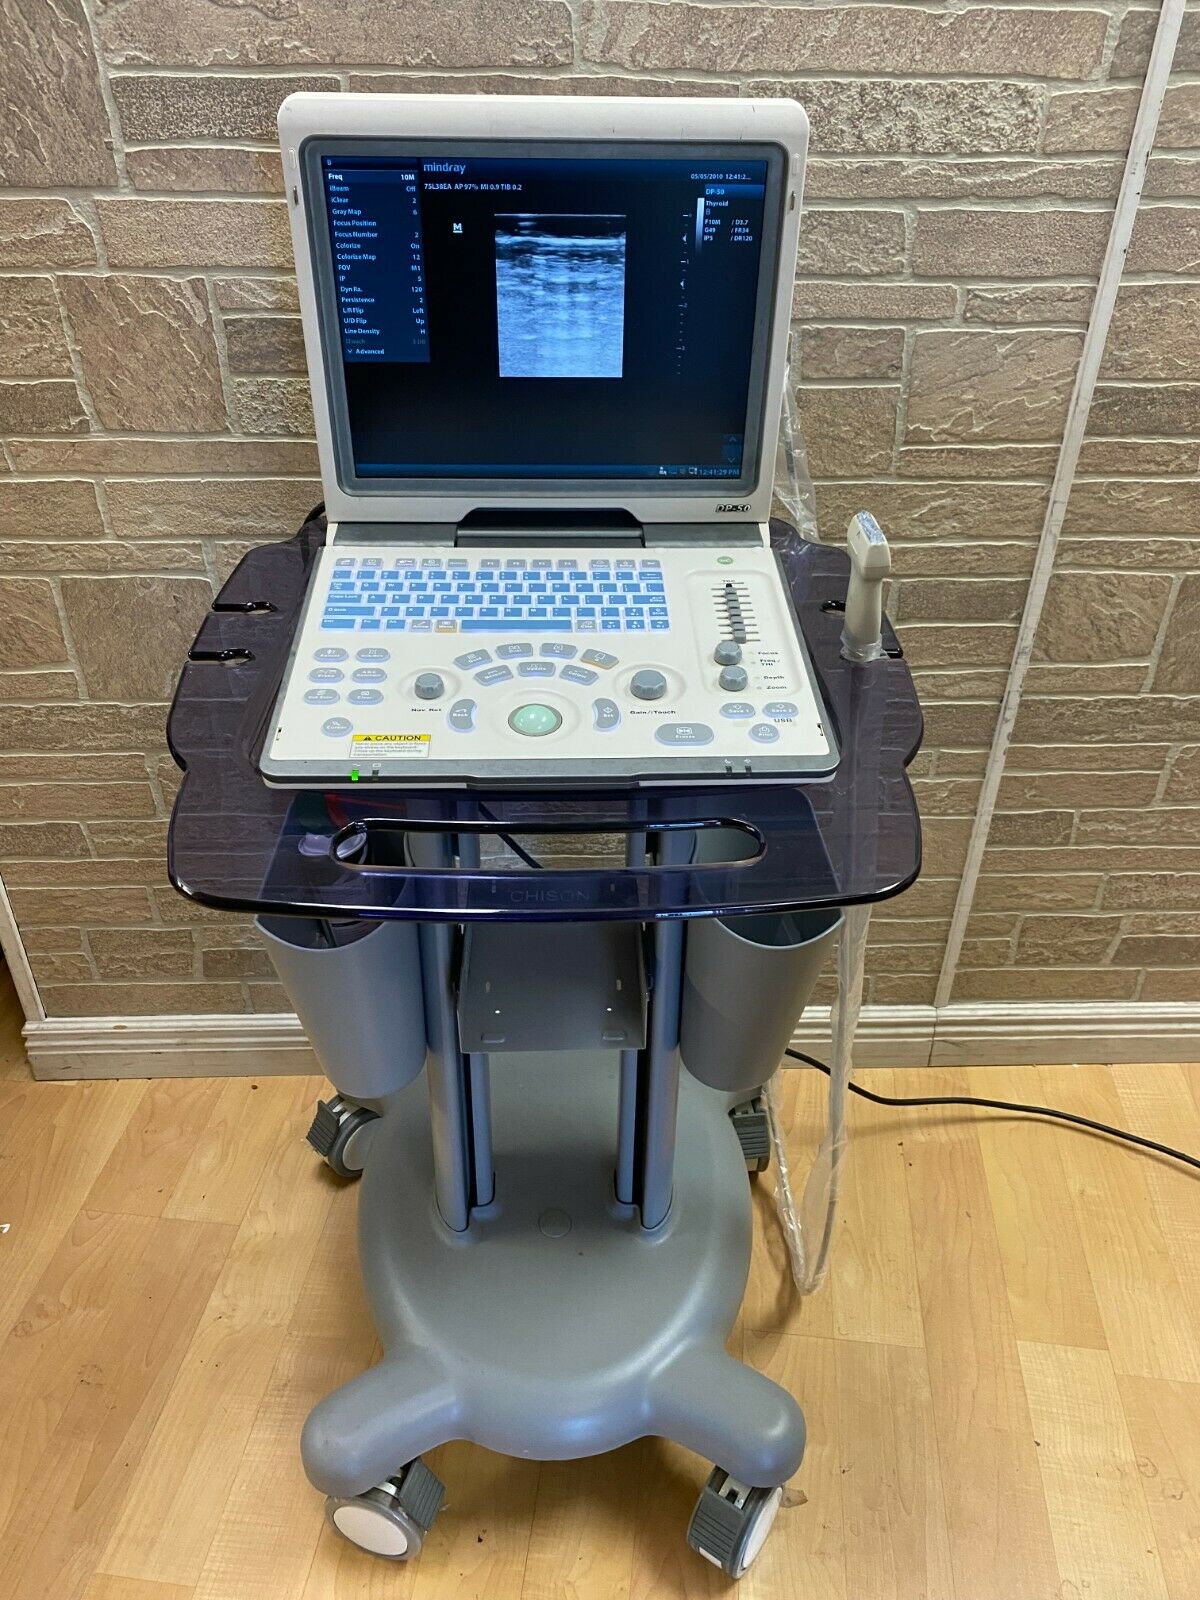

DIAGNOSTIC ULTRASOUND MACHINES FOR SALE

Mindray DP50 Ultrasound with Linear Array Probe 75L38EA

Sale price$ 10,498.00

Regular price$ 11,198.00